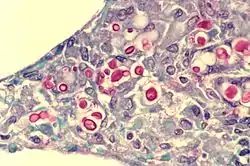

There are three major types of alveolar cell. Two types are pneumocytes or pneumonocytes known as type I and type II cells found in the alveolar wall, and a large phagocytic cell known as an alveolar macrophage that moves about in the lumens of the alveoli, and in the connective tissue between them. Type I cells, also called type I pneumocytes, or type I alveolar cells, are squamous, thin and flat and form the structure of the alveoli. Type II cells, also called type II pneumocytes or type II alveolar cells, release pulmonary surfactant to lower surface tension, and can also differentiate to replace damaged type I cells.[12][15]

Type I cells are the larger of the two cell types; they are thin, flat epithelial lining cells (membranous pneumocytes), that form the structure of the alveoli.[3] They are squamous (giving more surface area to each cell) and have long cytoplasmic extensions that cover more than 95% of the alveolar surface.[12][17]

Type I cells are involved in the process of gas exchange between the alveoli and blood. These cells are extremely thin – sometimes only 25 nm – the electron microscope was needed to prove that all alveoli are lined with epithelium. This thin lining enables a fast diffusion of gas exchange between the air in the alveoli and the blood in the surrounding capillaries.

Type II cells

Type II cells are cuboidal and much smaller than type I cells.[3] They are the most numerous cells in the alveoli, yet do not cover as much surface area as the squamous type I cells.[18] Type II cells (granulous pneumocytes) in the alveolar wall contain secretory organelles known as lamellar bodies or lamellar granules, that fuse with the cell membranes and secrete pulmonary surfactant. This surfactant is a film of fatty substances, a group of phospholipids that reduce alveolar surface tension. The phospholipids are stored in the lamellar bodies. Without this coating, the alveoli would collapse. The surfactant is continuously released by exocytosis. Reinflation of the alveoli following exhalation is made easier by the surfactant, which reduces surface tension in the thin fluid lining of the alveoli. The fluid coating is produced by the body in order to facilitate the transfer of gases between blood and alveolar air, and the type II cells are typically found at the blood–air barrier.[19][20]

Alveolar macrophages

The alveolar macrophages reside on the internal luminal surfaces of the alveoli, the alveolar ducts, and the bronchioles. They are mobile scavengers that serve to engulf foreign particles in the lungs, such as dust, bacteria, carbon particles, and blood cells from injuries.[24] They are also called pulmonary macrophages, and dust cells.